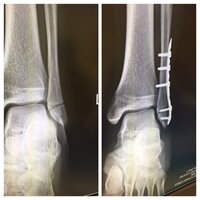

骨折の手術治療は? 術中写真固定後 / 術後レントゲン 骨折部のずれが大きい場合や骨折部が粉砕して不安定な骨折の場合は手術を選択します。骨折部にプレートとスクリューという金属を挿入して固定し骨折後に入れたボルトを抜く時入院期間はどれくらいかかる? ゐろはにほけん 「抜釘術」とは?術後はリハビリテーションは必要? 骨折の固定手術後にワイヤーを抜く!痛みはあるの? ゐろはにほけん; 50歳の男です。 今年1月に、脛骨骨折の抜釘手術を受けて3カ月が過ぎました。 執刀医からは、スクリューを本近く入れていて、その穴が開いているので、激しい動きはしない様に支持されています。 この穴は、何時頃に復元して、そこ

腓骨骨折のプレート手術 ボルトの位置について 日程前に腓 Yahoo 知恵袋